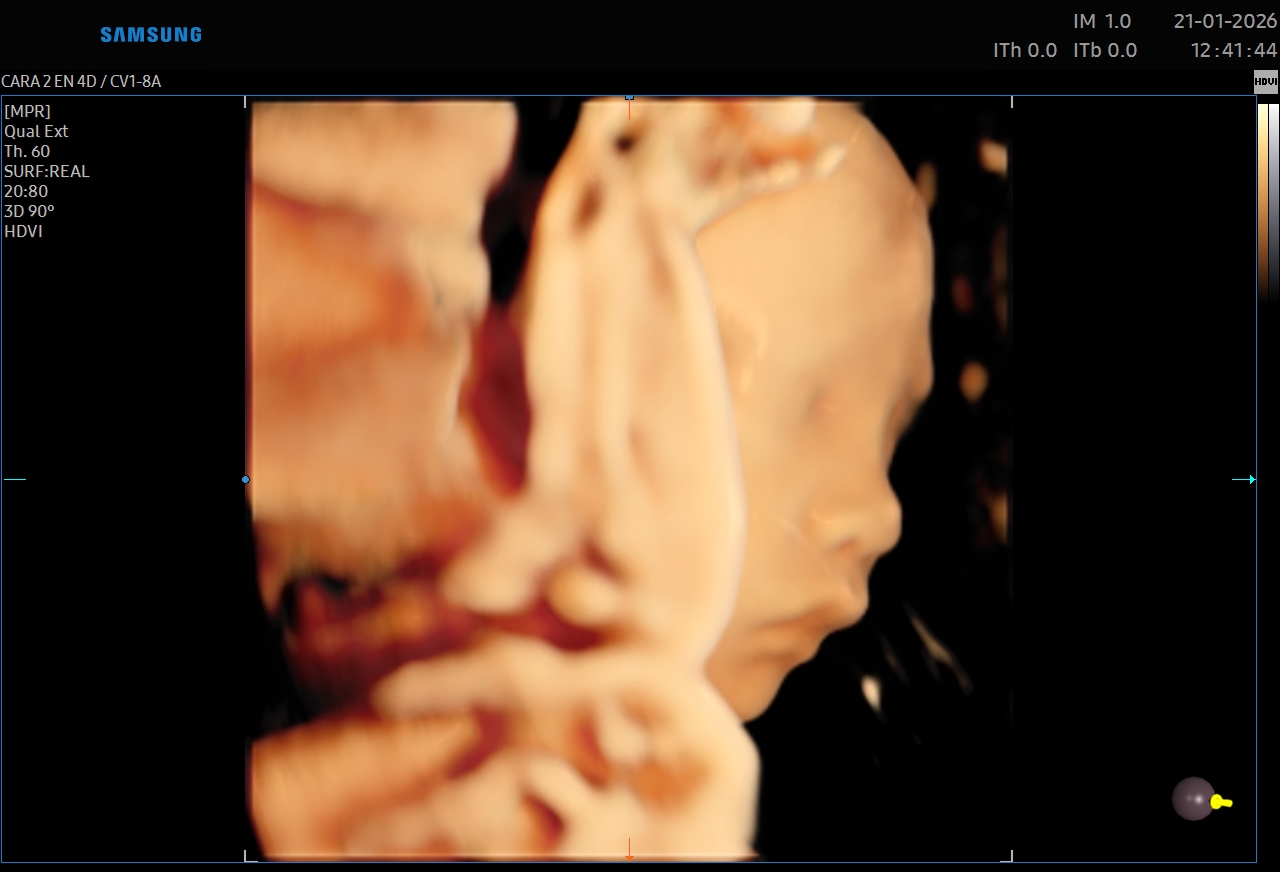

Ecografías 5D

La ecografía 5D es una experiencia única que te permite ver a tu bebé con un nivel de realismo sorprendente, capturando detalles como sus gestos, expresiones y movimientos en tiempo real.

Gracias a esta tecnología avanzada, podrás observar el rostro de tu bebé con mayor claridad, creando un vínculo emocional aún más especial antes de su nacimiento. Es el momento perfecto para compartir con tu familia y guardar recuerdos inolvidables de esta etapa tan importante.

Además de ser una experiencia hermosa, este estudio se realiza con equipos de alta tecnología y bajo supervisión médica, garantizando seguridad tanto para la mamá como para el bebé.